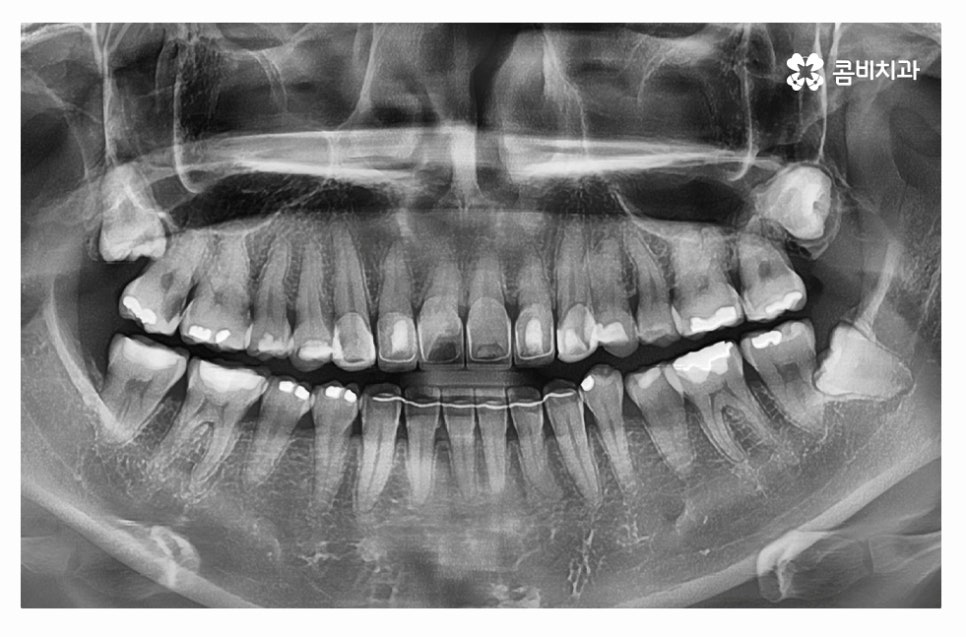

현대인들은 나날이 턱뼈가 좁아지고 있고 사랑니 자체가

아예 자라지 않는 경우도 있지만 현실적으로는

매복 혹은 누운 사랑니 발치해야 하는 분들이 늘고 있는데요.

발치를 해야 한다면 당장 두렵게 느껴지는 분들도 많겠지만

오늘 사례에서 보신 것처럼 어금니에 충치나 잇몸질환 등을

유발할 수 있는 만큼 매년 주기적으로 검진 받는 것을 실천하고

스케일링을 받는 것이 중요하다고 할 수 있어요.

사랑니 발치를 하는 것이 좋겠다고 치과 의사의 소견이 있으셨다면

너무 늦지 않게 시술받는 것이 좋으며

사랑니는 발치도 잘해야 하지만 회복 기간도 중요하다는 점에서

잇몸이 건강한 상태에서 치과를 찾는 것이 유리하다고 할 수 있어요.